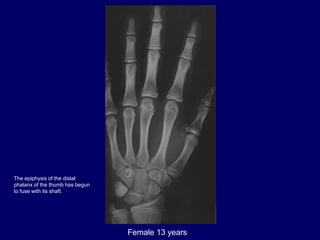

Female 13 years

The epiphysis of the distal

phalanx of the thumb has begun

to fuse with its shaft.